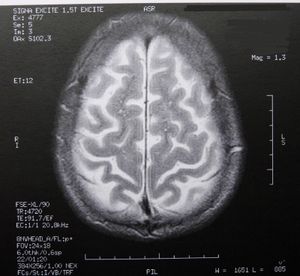

Gehirn: Rätsel der Faltung gelöst (Foto: pixelio.de, Dieter Schütz) |

Cambridge (pte001/20.08.2014/06:00) Forscher der Harvard University http://harvard.edu haben herausgefunden, wie das Gehirn seine gefaltete Form erhält. Die oberste Schicht des menschlichen Denkorgans, der Kortex, wird als graue Zellen bezeichnet. Säugetiere mit größeren Gehirnen verfügen über einen stärker gefalteten Kortex. Das menschliche Gehirn ist das mit den meisten Falten. Die Forschungsergebnisse wurden im Fachmagazin "PNAS" http://pnas.org veröffentlicht.